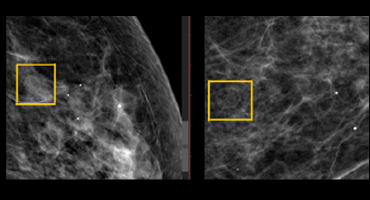

Mamografía

QUISTE OLEOSO